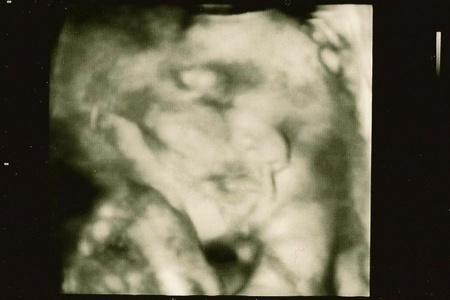

A terhességem alatt bekövetkezett legszebb dolog pedig tegnap történt velem. A 30-32. heti magzati fejlődés ellenőrzését szolgáló ultrahangot egybekötöttük egy 4D-s felvétellel. Mit mondhatnék? Gyönyörű ez a gyerek. Kedvtelve nézegette az idős szonográfus-orvos is, és többször elismételte: „gratulálok, igazán nagyon szép kisbabájuk lesz.” Láttam hasonlóságot és különbséget is Csani hasonló korú felvételeit felidézve, ami különösen jó, mert egyik oldalról éreztem, hogy ismerős nekem ez a kisfiú, míg másik oldalról felfogtam azt, hogy egy teljesen új emberi lényt hordok a szívem alatt, akinek a kis egyéniségét, személyiségét boldogság lesz felfedezni és megismerni.

Csodás felvételek készültek, látszik, amint a kisfiam a finom kis pofikáját az öklére hajtva Csipkerózsika módra szunyókál, a térdére könyökölve tartja az arcát, akárcsak Rodin Gondolkodója, vagy éppen kinyújtja a csöpp nyelvét, grimaszol, vagy mosolyra húzza a száját. Ismerősek voltak a cirkuszkerítés mintájára szétterpesztett lábujjak, melyeket jól ismerek már egy negyvenkettes és egy huszonnégyes lábikóról. Apja fia ez is. Legyen akkor Micó baba. Az én Micó babám.